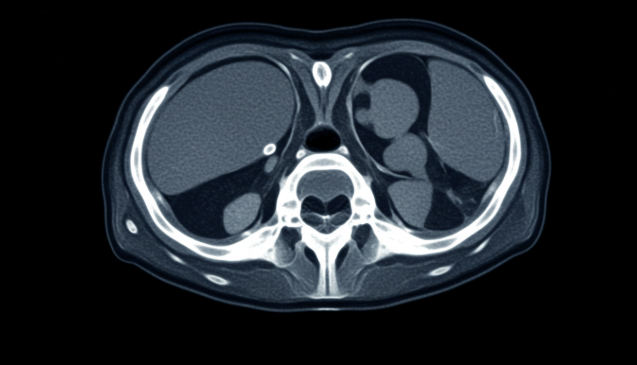

병원에서 CT(컴퓨터 단층 촬영) 검사를 받아보면 종종 영상이 또렷하거나, 때로는 희미하게 보이는 차이를 경험하게 됩니다. 사실 이 차이는 단순한 촬영 방법 때문만이 아니라, CT 시스템의 핵심 부품인 '검출기' 기술 차이 때문입니다. 오늘은 '영상 선명도'를 결정짓는 CT 검출기의 고급 기술에 대해 조금 더 깊이 있게 정리해보려 합니다. 복잡하게만 느껴졌던 CT 시스템의 숨은 이야기를 쉽고 체계적으로 이해할 수 있도록 풀어드리겠습니다.

CT 시스템의 검출기는 간단히 말하면 'X선을 받아 영상 신호로 바꿔주는 장치'입니다. 촬영 대상(사람이나 물체)을 통과한 X선이 검출기에 도달하면, 검출기는 이 에너지를 디지털 신호로 변환하여 컴퓨터가 해석할 수 있도록 합니다. 검출기의 성능은 크게 다음 요소로 결정됩니다.

CT 영상의 선명도는 검출기의 고급 기술에 의해 크게 달라집니다. 최근 주목받는 핵심 기술 몇 가지를 소개합니다. 1. 직접 변환 검출기(Direct Conversion Detector) 기존 섬광체 방식 대신, X선을 직접 전기 신호로 변환하는 기술입니다. '카드뮴 텔루라이드(CdTe)'나 '카드뮴 아연 텔루라이드(CZT)' 같은 반도체 물질을 사용하여 변환 과정에서 발생하는 신호 손실을 최소화합니다. 덕분에 훨씬 선명하고 노이즈가 적은 영상이 만들어집니다. 2. 소형 픽셀화(Miniaturized Pixel Technology) 검출기 내 픽셀 크기를 미세하게 줄이면 더 높은 해상도를 얻을 수 있습니다. 더 작은 구조물까지 구분할 수 있게 되어, 초기 병변이나 미세 병소 탐지에 큰 도움이 됩니다. 하지만 픽셀 크기가 작아질수록 노이즈 관리가 더 중요해집니다. 3. 듀얼 에너지 CT 검출기(Dual-energy CT) 두 가지 서로 다른 에너지의 X선을 동시에 사용하여 조직 성분이나 병변의 특성을 구분할 수 있게 해주는 기술입니다. 특수한 검출기 설계 덕분에 다양한 재질 분석이 가능해졌습니다. 4. 저 노이즈 고효율 재료 개발 기존보다 더 고효율로 X선을 흡수하고, 불필요한 신호를 억제하는 신소재 검출기들이 연구되고 있습니다. 예를 들어, 빠른 응답 속도와 높은 감도를 동시에 갖춘 '라루늄 브로마이드(LaBr₃)' 기반 재료 등이 주목받고 있습니다. 이처럼 영상 선명도를 좌우하는 것은 단순히 기계적인 촬영 기술이 아니라, 검출기의 세밀한 기술력에서 비롯됩니다. 특히 최신 CT 장비들은 검출기의 발전 덕분에 과거보다 훨씬 선명하고 정확한 진단이 가능해졌습니다.